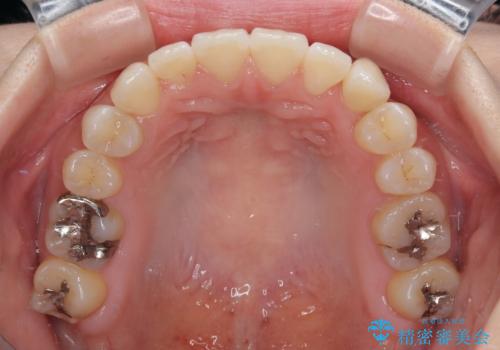

上顎骨を拡大することで、八重歯やデコボコを歯列に収めることができ、下顎の歯が外に位置していた奥歯の咬み合わせも改善することができました。

スペースも短期間に獲得できるため、1年程度で治療を終えることができました。